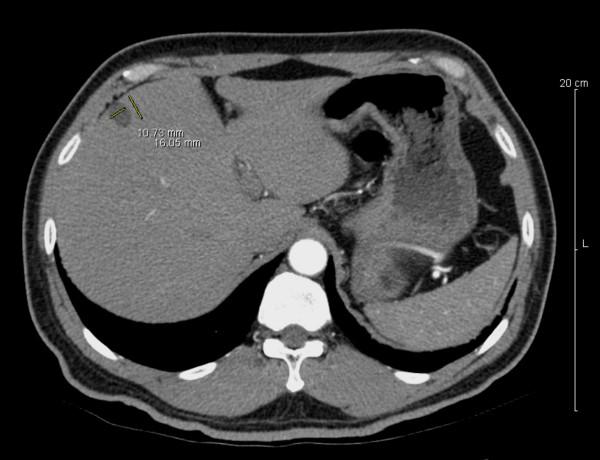

Ciliated hepatic foregut cyst is a rare condition almost always found incidentally on a computerized tomography scan or at autopsy. Rarely, portal vein compression can be a presenting finding. The cysts are usually unilocular and occur with greater frequency in males. There is a predilection for the left lobe. The cysts average 3 cm in size.

We present in this case report a ciliated hepatic foregut cyst found incidentally in the setting of renal carcinoma. The patient was a man known to have a large renal mass, assumed to be cancer, and a liver mass suspicious for metastatic disease. This liver mass was cystic and upon further analysis showed ciliated epithelial lining. We describe the gross and histological appearance, as well as a brief discussion of ciliated hepatic foregut cysts.

纤毛肝前肠囊肿是一种罕见疾病,几乎总是在计算机断层扫描或尸检时偶然发现。门静脉受压很少作为首发表现。囊肿通常为单房性,男性中更常见。好发于左叶。囊肿平均大小为3厘米。

我们在此病例报告中呈现一例在肾癌背景下偶然发现的纤毛肝前肠囊肿。患者为一名男性,已知有一个大的肾肿物,推测为癌症,还有一个肝脏肿物怀疑为转移性疾病。这个肝脏肿物为囊性,进一步分析显示有纤毛上皮内衬。我们描述了大体和组织学表现,并对纤毛肝前肠囊肿进行了简要讨论。